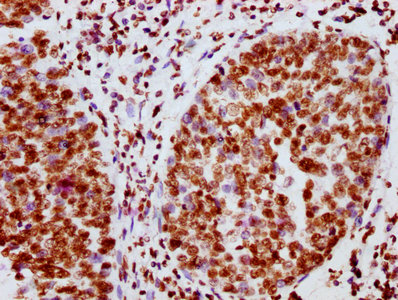

IHC image of CSB-RA011931A100phHU diluted at 1:100 and staining in paraffin-embedded human ovarian cancer performed on a Leica BondTM system. After dewaxing and hydration, antigen retrieval was mediated by high pressure in a citrate buffer (pH 6.0). Section was blocked with 10% normal goat serum 30min at RT. Then primary antibody (1% BSA) was incubated at 4℃ overnight. The primary is detected by a biotinylated secondary antibody and visualized using an HRP conjugated SP system.